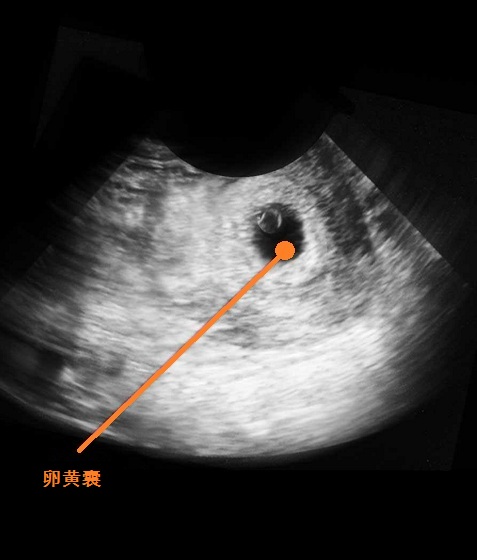

B超图

胚芽正在你的子宫深处迅速生长。这时候,宝宝的胚胎长度约0.4-0.5厘米,有一个小苹果籽大小,但是看起来还不像人,更像一只小蝌蚪。宝宝的心脏开始有规律的跳动及开始供血。